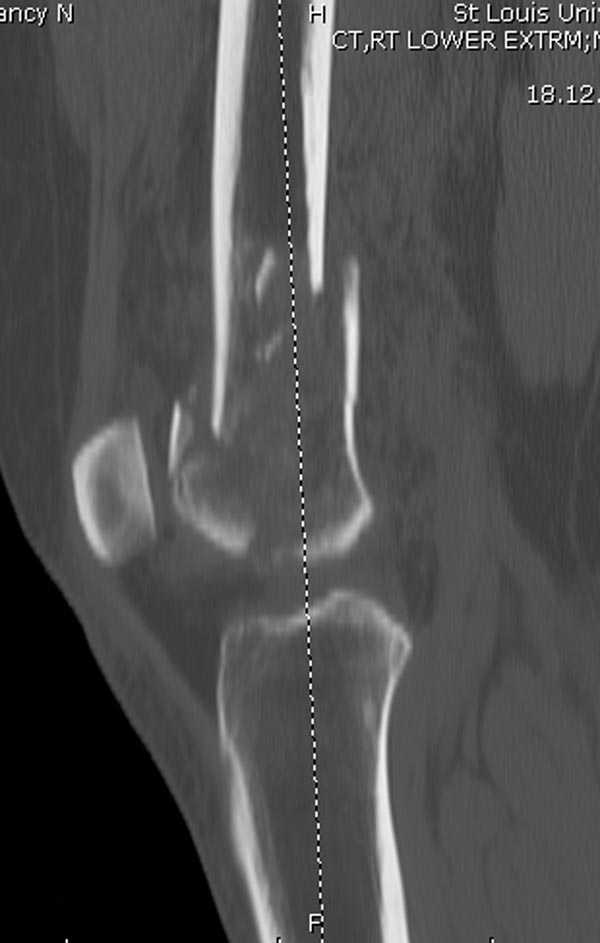

На профиле стало видно, что открываться придется, это перелом C3, хотя можно назвать и C2+, т.е. с еще и фронтальным раскалыванием одного мыщелка. Надо сделать медиальную артротомию, ступеньку на внутреннем мыщелке устранить, ввести либо несколько временных спиц спереди назад, или сразу винт вдоль эллипса мыщелка. А дальше как выше написано - дистрактор, и штифтовать. Учитывая наличие открытого колена - вполне уместно ретроградно.

Почти все компании имеют пластины с угловой стабильностью, начиная от Stryker, Zimmer NCB и DePuy Polyaxial Plate . Если у NCB шуруп блокируется специальной шайбой, то Polyaxial Plate имеет вариабельный угол введения шурупов.

Поэтому такие меж и над- мыщелковые переломы более предпочтительным считается фиксировать мыщелковыми пластинами

Устанавливается из малого разреза "не вскрывая сустав" со стороны латерального мыщелка, и Insertion Jig позволяет установить пластину "мостовидно" перкутанно в проксимальном отделе, "не вскрывая и не трогая" место перелома.